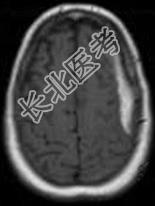

- 单项选择题女,71岁, 头晕,言语模糊, 2周前被摩托车撞伤,结合MRI图像选择最可能的诊断 ( )

D、亚急性硬膜下血肿

E、慢性硬膜下血肿